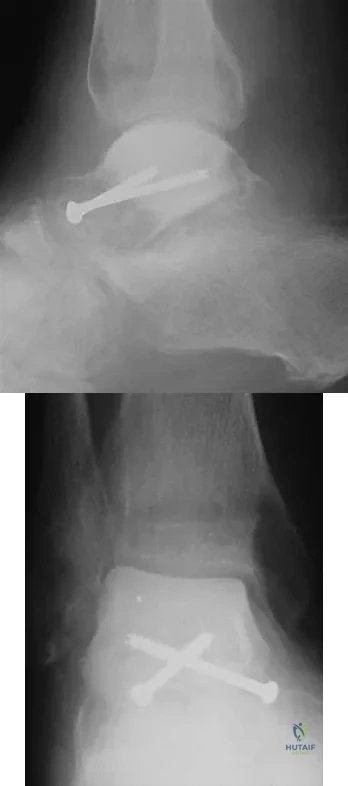

A 57-year-old man has had right ankle pain for the past 10 months following an injury that went untreated. Radiographs are shown in Figures 30a through 30c. Management should consist of

Explanation